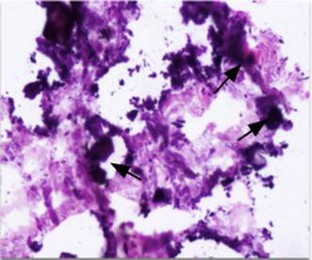

Fig. 1

Fig. 2

Fig. 3

Fig. 4

Fig. 5

Fig. 6

Fig. 7

Fig. 8

Fig. 9

Fig. 10